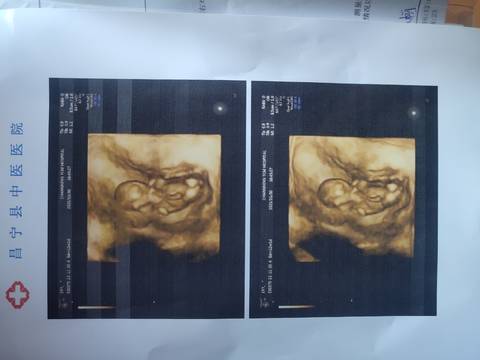

13周还要吃叶酸吗

journal_insert_pic_1675354196